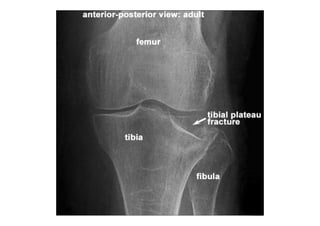

RADIOLOGIA DO

TRAUMA DO ESQUELETO

Referência: http://www.accessexcellence.org/RC/VL/